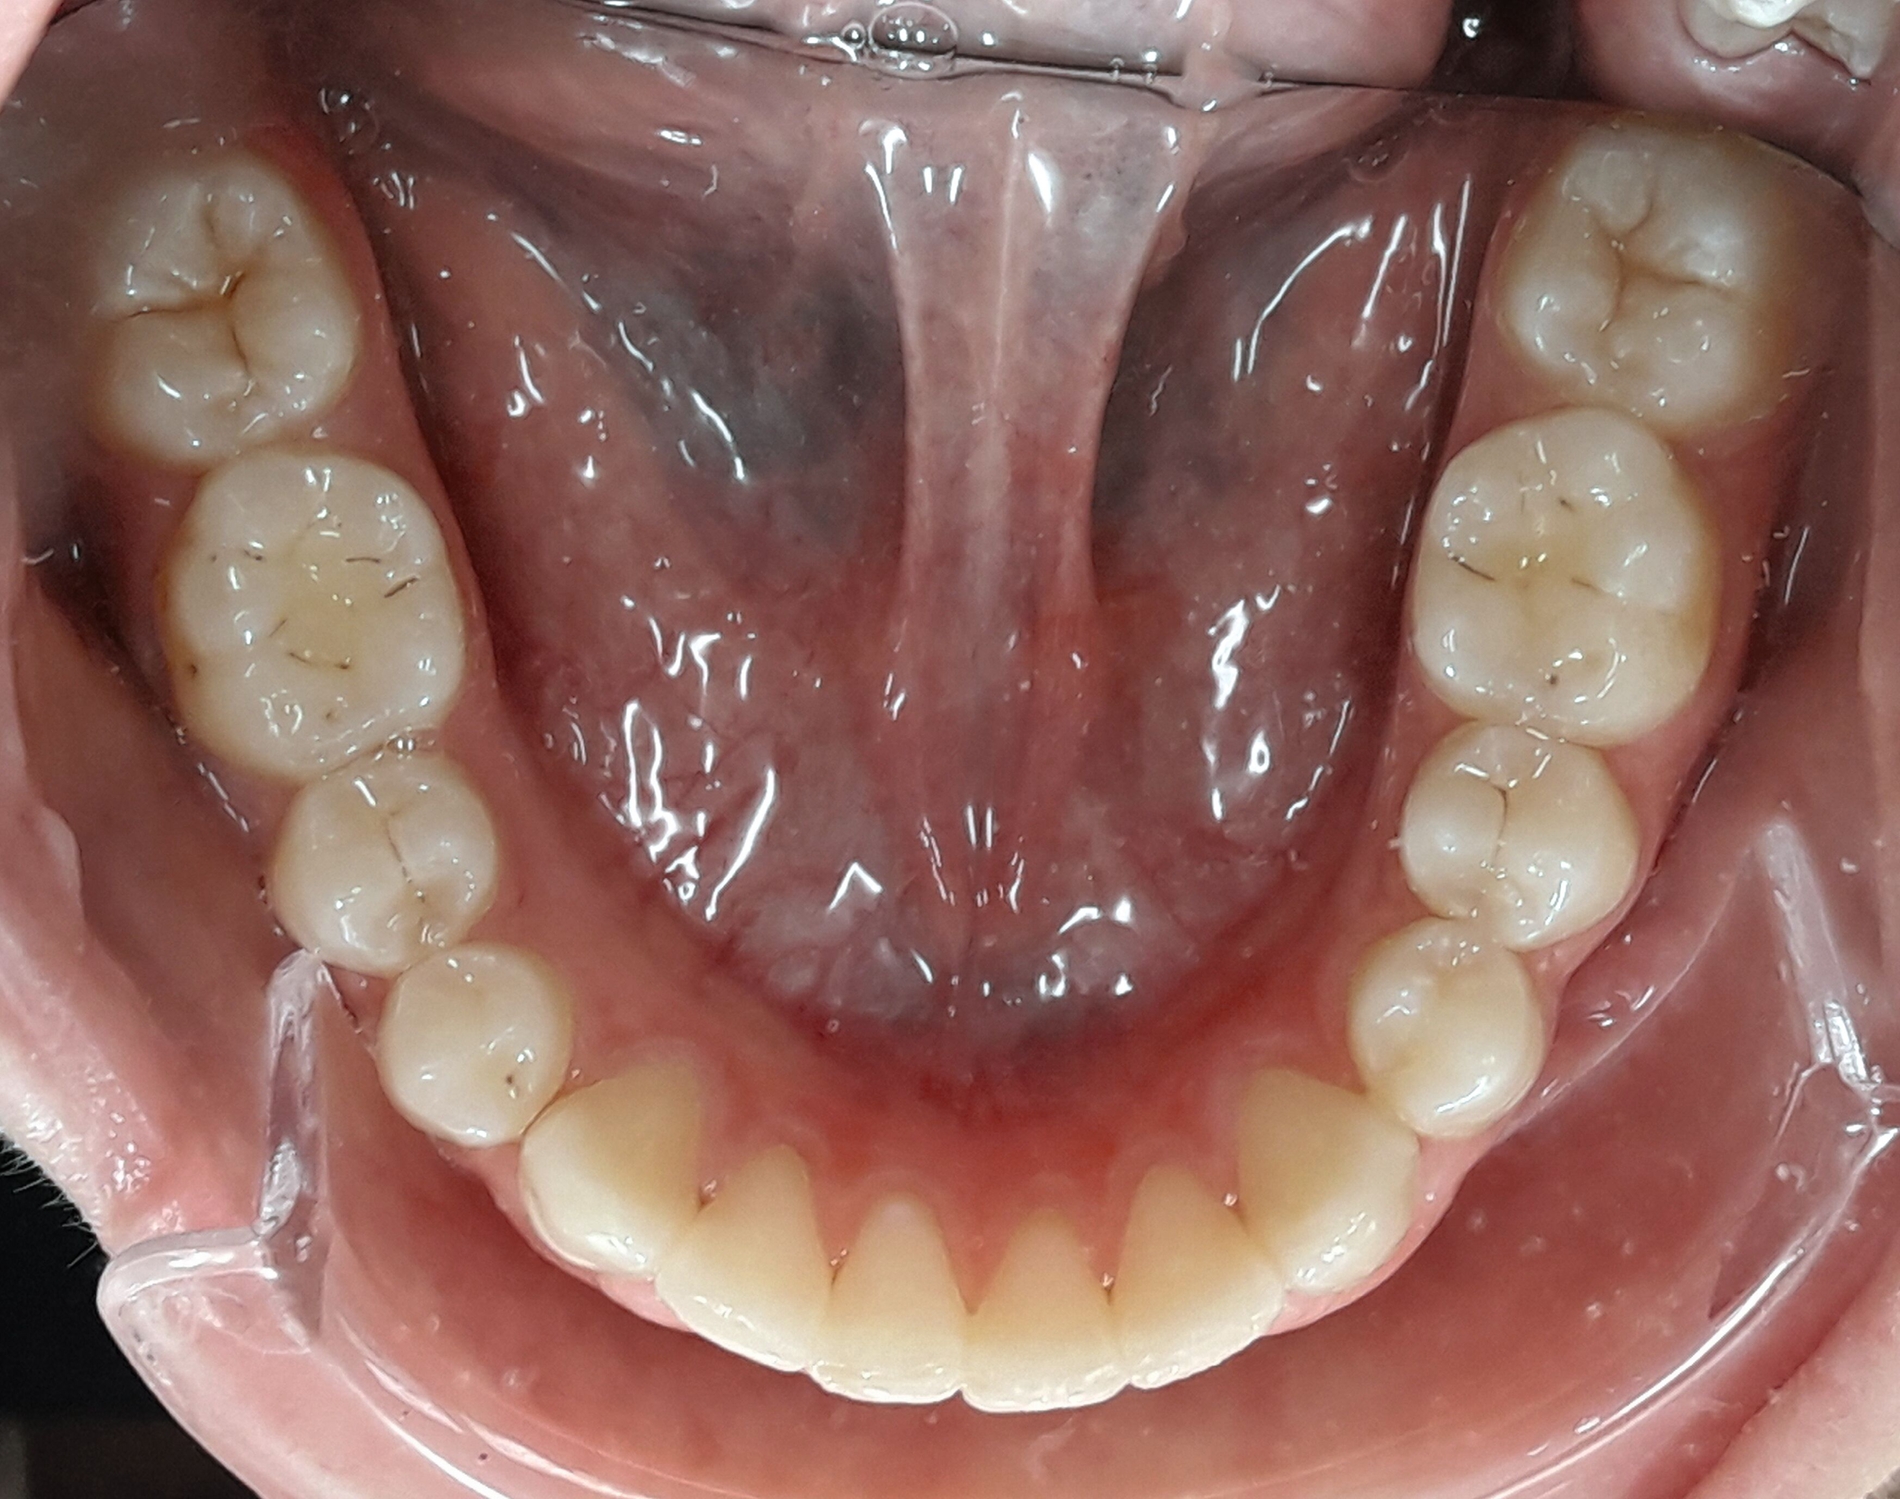

Im Februar 2019 wurde die kieferorthopädische Klinik von der Erstautorin übernommen. Bei der Auswertung der vorgefundenen Daten der Patientin wurde festgestellt, dass der linke obere zentrale Schneidezahn vor sechs Monaten extrahiert worden war. Die festsitzende Apparatur war im Oberkiefer bereits eingegliedert. Die Druckfeder zwischen Zahn 11 und 22 diente zur Lückenöffnung für den späteren prothetischen Ersatz des Zahnes 21. Auch auf den persistierenden linken Milcheckzahn war ein Bracket geklebt. Die Okklusion im Bereich der ersten Molaren war rechts und links neutral (Abbildung 2).